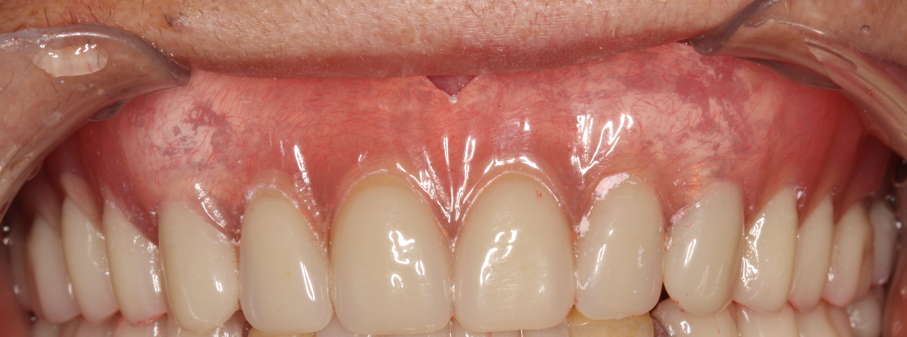

图片16.png

.总义齿